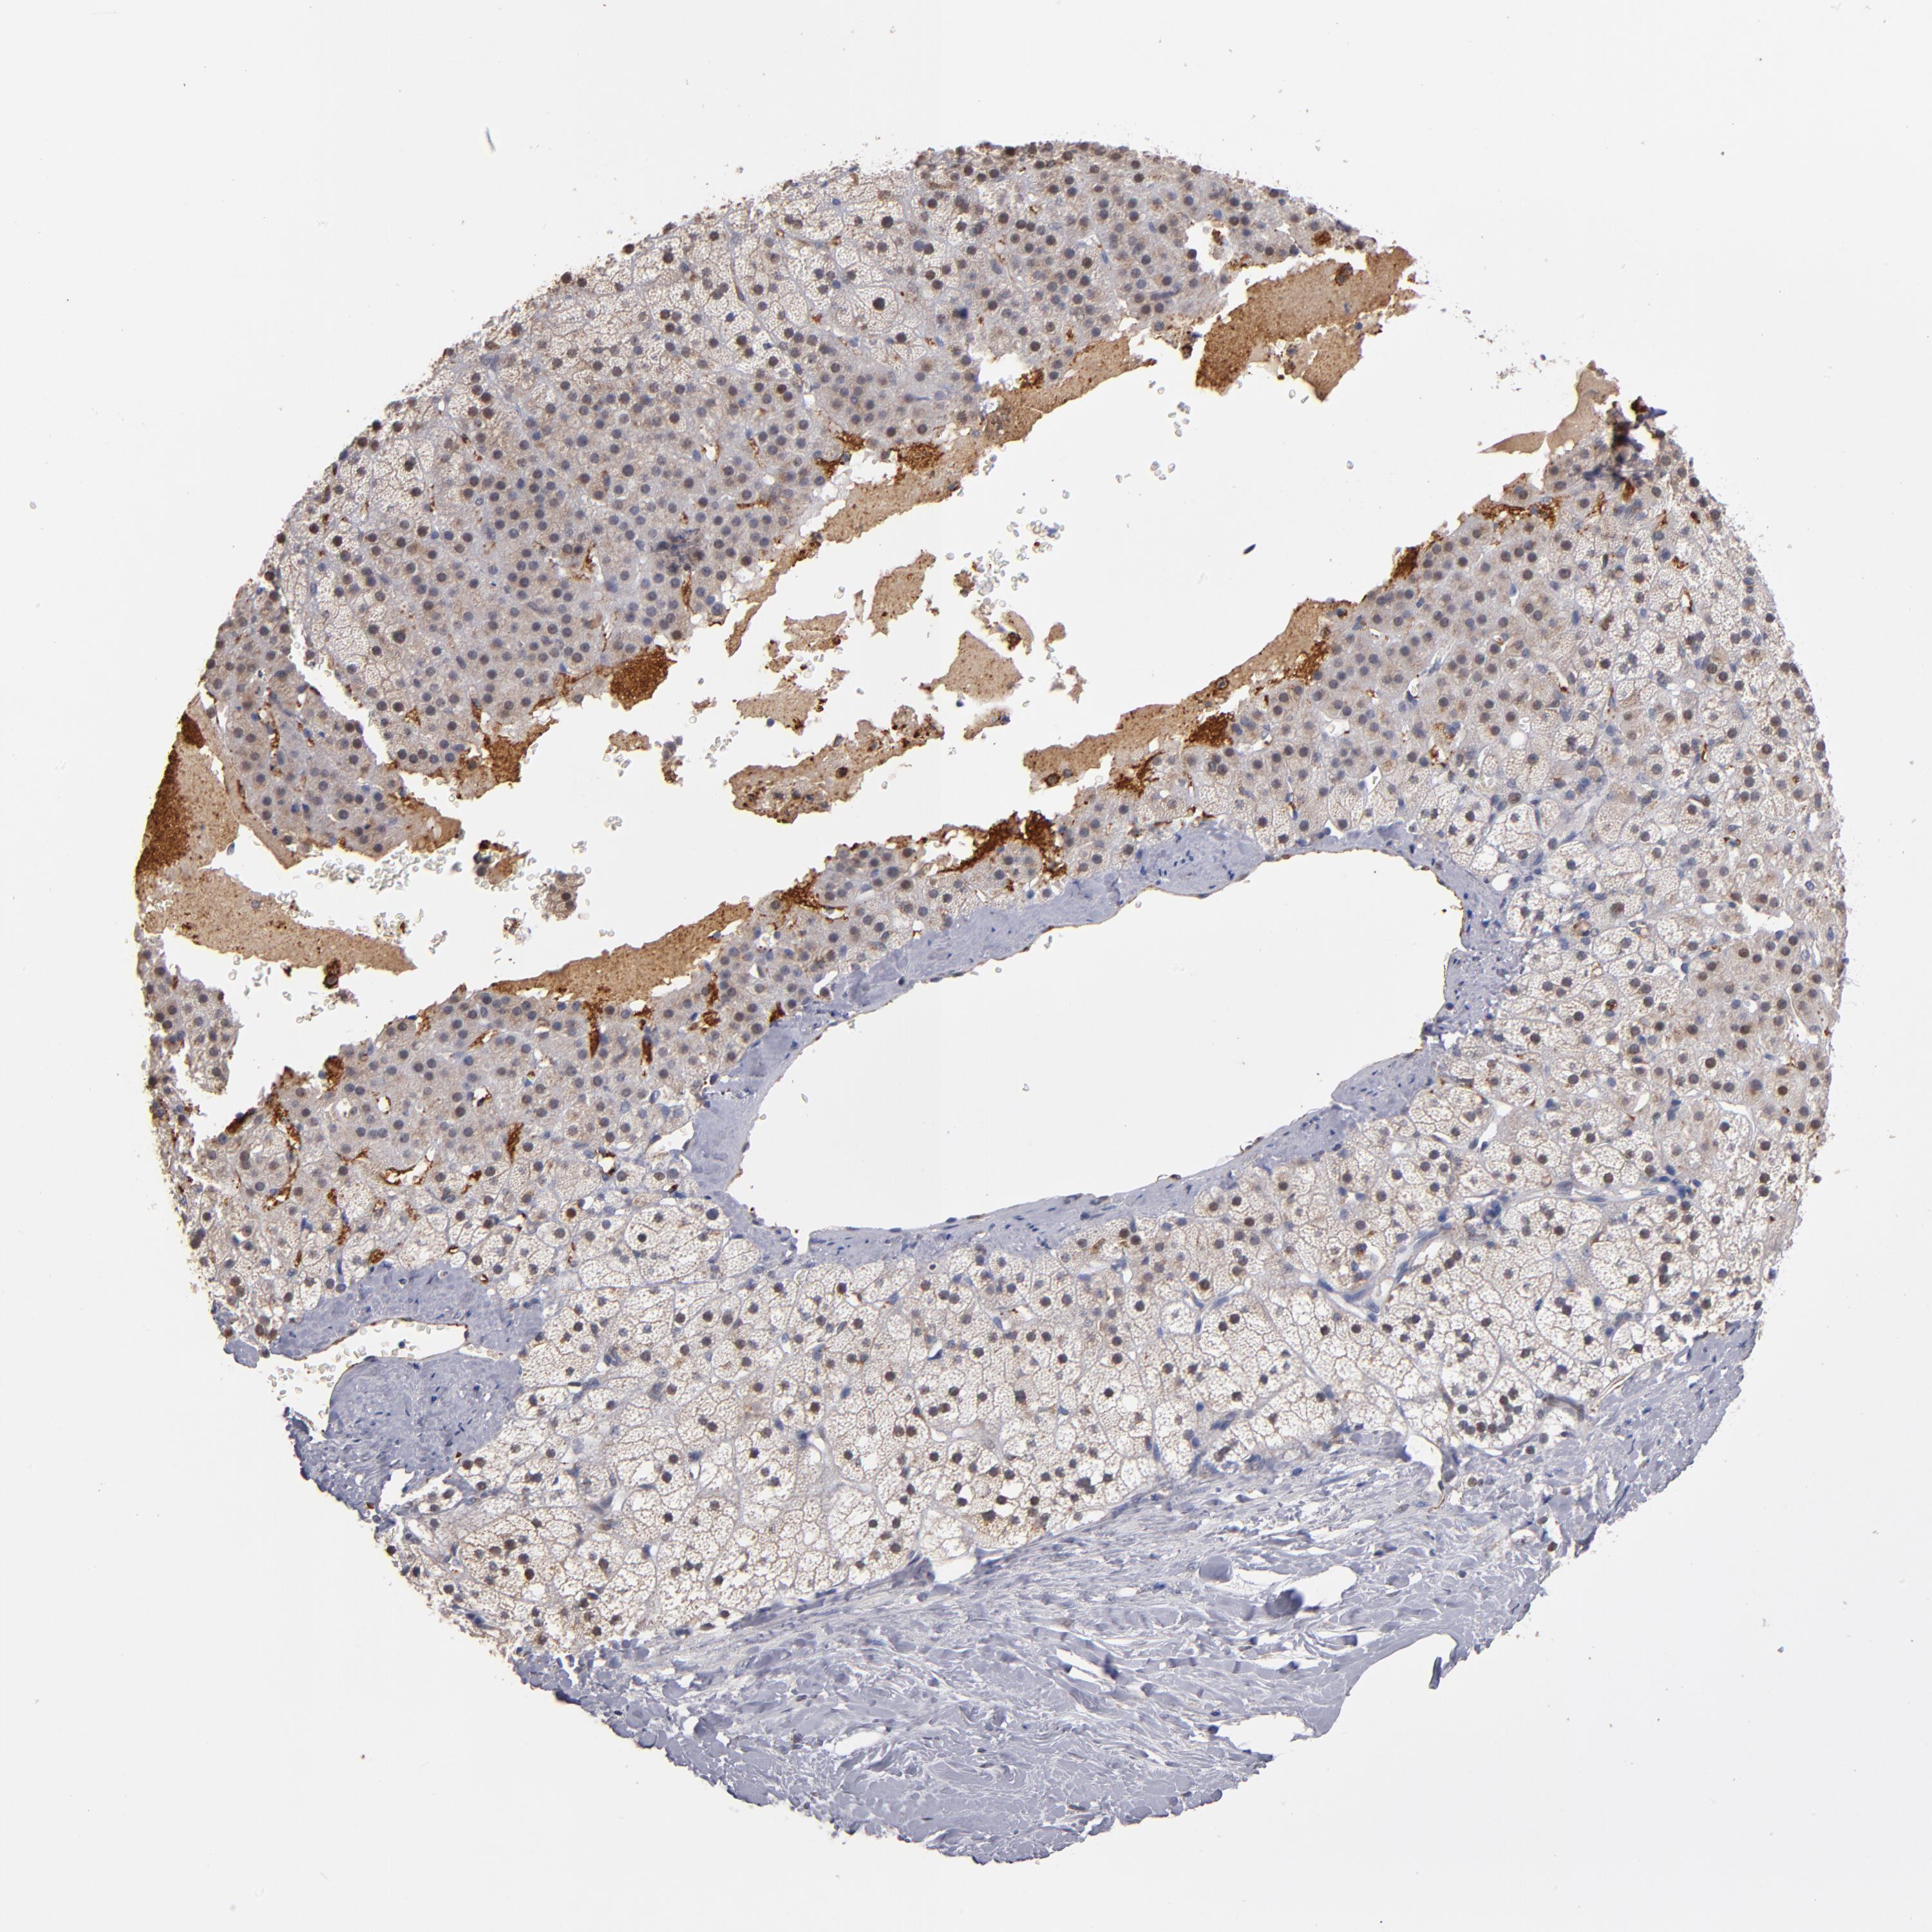

ADRENAL GLAND - Antibody stainingi

Antibody staining in the annotated cell types in the current human tissue is reported as not detected, low, medium, or high, based on conventional immunohistochemistry profiling in selected tissues. This score is based on the combination of the staining intensity and fraction of stained cells.

Each image is clickable and will lead to virtual microscopy that enables deeper exploration of all samples and also displays staining intensity scores, fraction scores and subcellular localization as well as patient and tissue information for each sample.

Antibody HPA002655Antibody HPA005990Antibody CAB002145

Glandular cells LowNot detectedNot detected